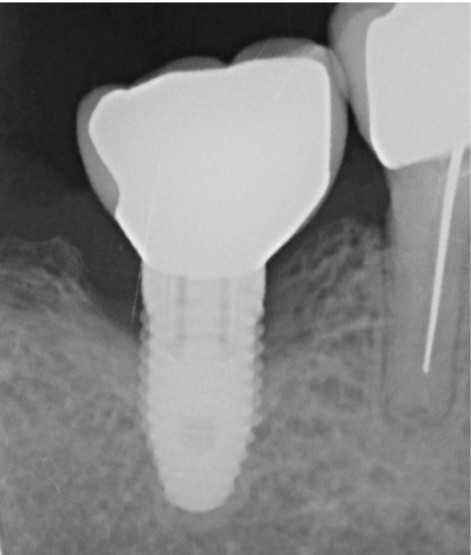

L’implant

- Péri-implantite sur l’implant 47, diagnostiquée en août 2022

- Poches de 6 à 7 mm

- Implant posé en 2017

- Nobel Replace Select RP (4,1 x 10 mm)